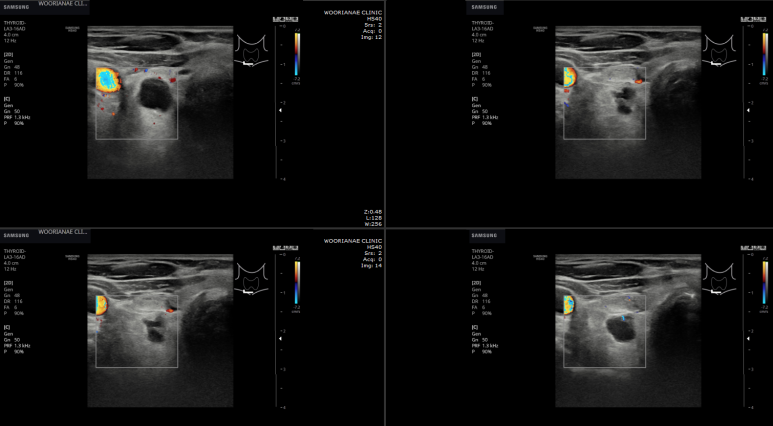

갑상선 초음파에서 오른쪽 갑상선 뒤쪽/아래로 결절?

위아래로 2개처럼 보이기도 하고..

2개가 아니라 연결되어 있으며 격벽처럼 관찰되는데... 1.75 cm

어두은 결절인지? 낭종인지? 구별이.. (낭종이 있을 위치가 아니라 생각을 하니..)

연속 사진으로 내측의 경계가 불규칙하거나 격벽 변화가 있는 모습

확대하면 두꺼운 벽처럼 보이는 부분도 있다. 거꾸로 아래쪽 어두운 곳은 낭성 변화